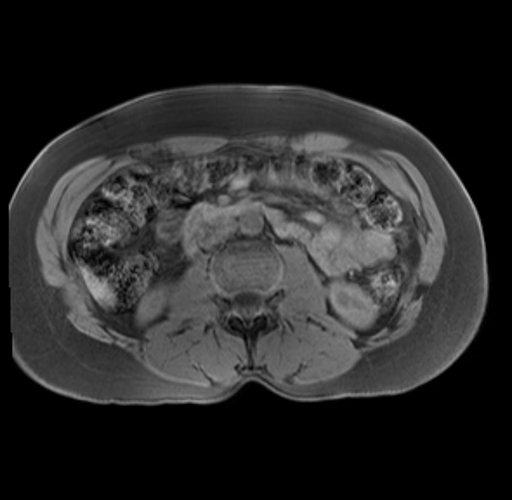

Imaging Analysis

Look through the patient's CT scan to identify any areas of concern for the necessary procedure.

Based on your CT findings, which issue(s) are present and would give reason for "planned slowing down moment(s)" in this case?